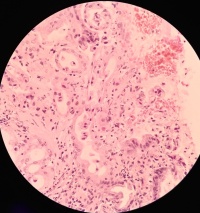

胃角溃疡活检

性别年龄53临床诊断

一般病史胃角溃疡

标本名称活检

大体所见灰白

粘膜慢性活动性炎

没有恶性病变。

考虑:急性炎症修复性反应。

• 王新安:  再看图12与13,腺癌不排除。

第一次的发图3那样的区域还是有些让人放心不下,片子这个颜色,分辩起有来点困难,建议重切重染,看清楚了再发,